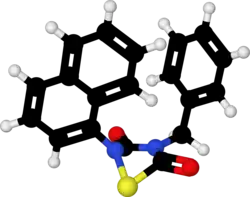

Tideglusib

| Formula | C19H14N2O2S |

| Molar mass | 334.39 g·mol−1 |

| 3D model (JSmol) | |

Tideglusib (NP-12, NP031112) is a potent and irreversible[1] small molecule glycogen synthase kinase 3 (GSK-3) inhibitor.[2]